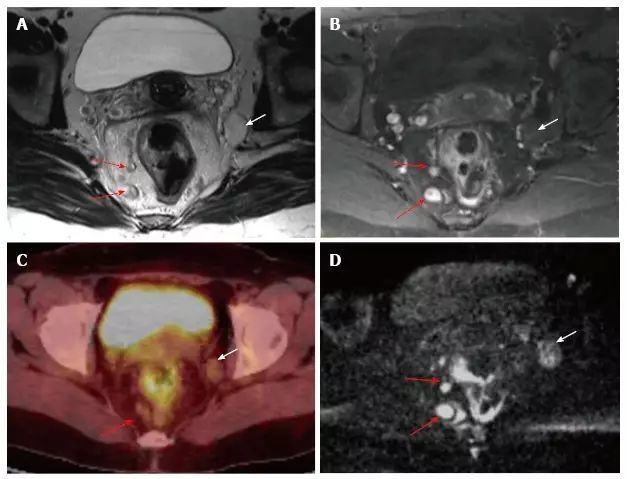

图片

图 16. 直肠系膜和直肠系膜外淋巴结受累。A. T2 加权;B. T1 加权造影增强轴向 MR 图像;C. 18 F-FDG PET-CT;D. DWI 在直肠系膜内(红色箭头)和直肠系膜外(白色区域)显示可疑淋巴结。直肠系膜外淋巴结在 DWI 上比 T2W 和 T1W 序列更为明显。